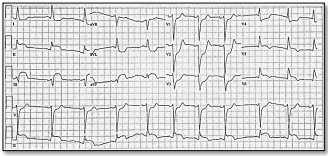

Paciente de 55 anos, sexo feminino e obesa,

no décimo dia pós-operatório de cirurgia de

Wertheim-Meigs para tratamento de neoplasia

de endométrio. Apresenta taquidispneia de

início súbito, dando entrada no PS com PA de

160 x 90 mmHg, FC 120 bpm, SpO2 88% com

O2 a 3L/min. Radiografia simples de tórax

sem alterações. O ECG apresentava o

seguinte traçado:

Diante dos dados apresentados, o diagnóstico mais provável é de